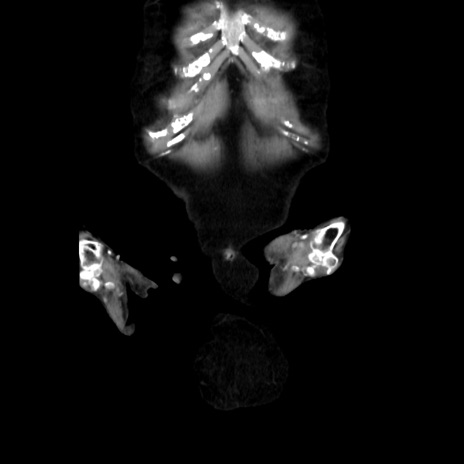

症例40(冠状断像)

【症例】90歳代女性

【主訴】腹痛・嘔吐

【現病歴】 食欲低下、嘔吐があり昨日他院受診。肺炎と診断され入院となる。入院後より腹部全体に圧痛あり。胃管留置され経過みていたが、症状持続するため、

当院転院となる。

【既往歴】胸椎圧迫骨折、胆石症

【身体所見】腹部:中央に激痛あり、圧痛あり、反跳痛不明

【データ】WBC 17100、CRP 18.82

矢状断像